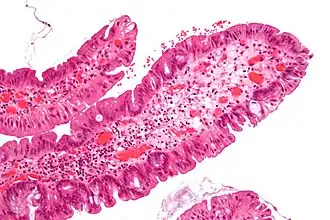

Villous adenoma 15%[16] to 40%[15] Over 75% villous[14]

The villous subdivision is associated with the highest malignant potential because they generally have the largest surface area. (This is because the villi are projections into the lumen and hence have a bigger surface area.) However, villous adenomas are no more likely than tubular or tubulovillous adenomas to become cancerous if their sizes are all the same.[18]